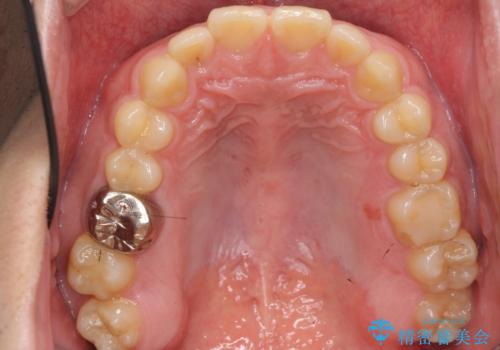

- 前歯の噛み合わせが反対になっていること、前歯の見た目の改善を希望され来院されました。

詳細な矯正検査の結果、顎の歪みが見られたため大きく歯を動かす治療ではなく前歯を主に並べることで前歯の前後関係を改善していきます。

前歯を主に動かす部分矯正であることからマウスピース矯正インビザラインによる治療を計画します。

マウスピース矯正はオーダーメイドのマウスピースを作成して矯正することができるため、部分的な矯正治療や仕上がりのイメージなどを掴んでいただくことが可能です。